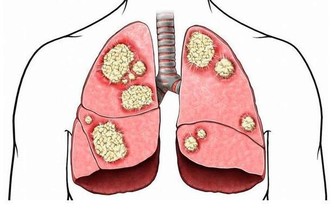

四、骨骼強壯,聽力好

腎主骨,骨靠腎精滋養,腎好骨才好,同時在出現耳鳴耳聾聽力下降一般就有可能是因為腎陰虛導致。